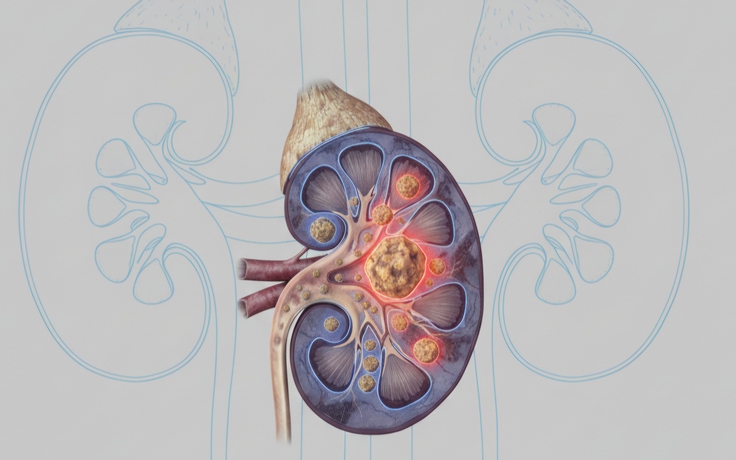

Nguyên nhân gây ra sỏi thận và cách điều trị